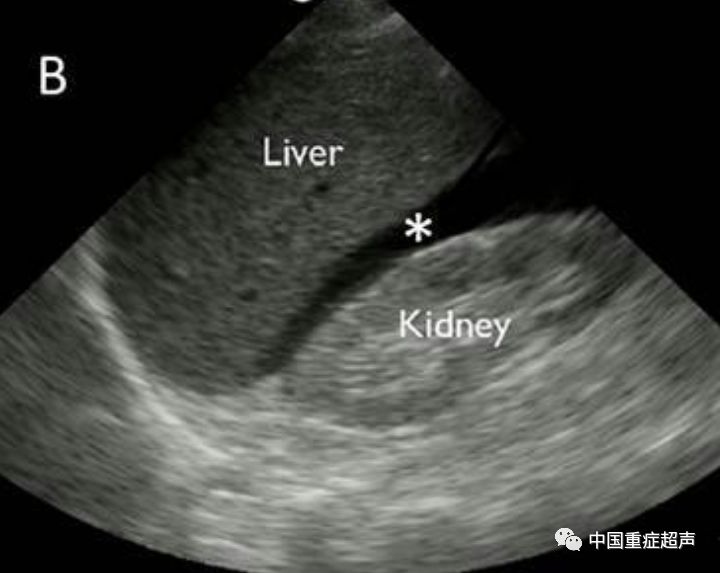

3 肝肾隐窝积血.jpg

间隙,左肾下极(左结肠旁沟)(7615雪花处为脾周及脾肾隐窝的积液)4